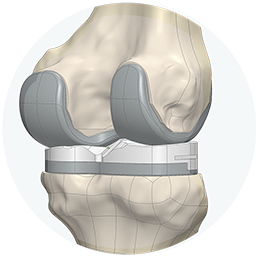

Consigue una sensación más natural

Prótesis de rodilla 3D está diseñada para seguir la forma y el contorno de la rodilla de cada paciente, proporcionando un mayor potencial para su rodilla con una sensación más natural.